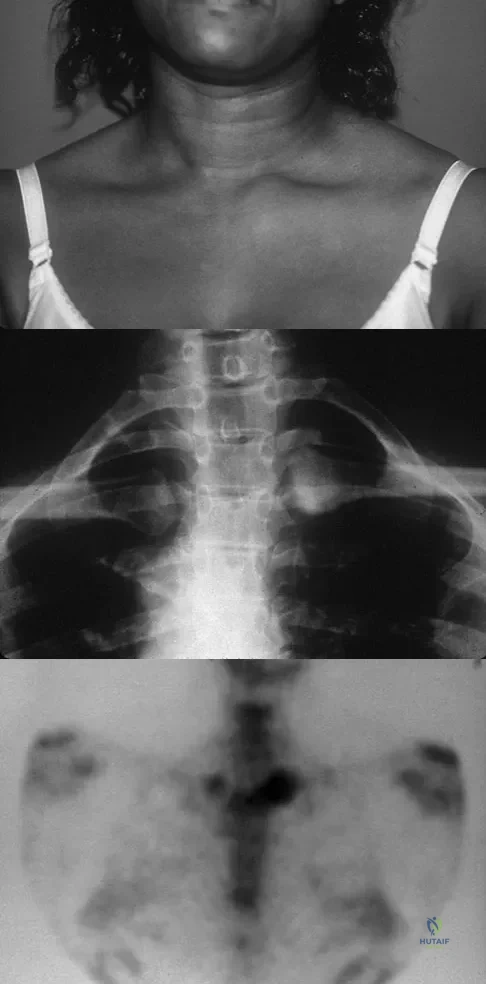

A 52-year-old woman reports mild pain localized to the left sternoclavicular joint. History is notable for chronic renal failure requiring dialysis for the last 5 years. A clinical photograph, chest radiograph, and bone scan are shown in Figures 58a through 58c. What is the most likely diagnosis?